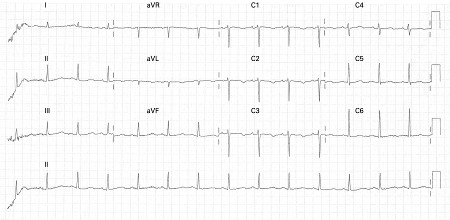

ECG findings in type 1 long QT syndrome

From the collection of Dr James P. Daubert